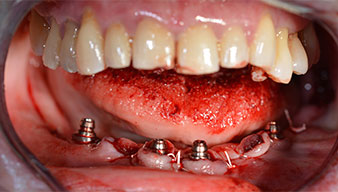

Nach der Entfernung der Unterkiefer-Restbezahnung erfolgte die krestale Schnittführung von Regio 37 bis Regio 47.

Zunächst wurde das Foramen mentale als limitierende anatomische Struktur dargestellt und die krestale Kortikalis mit dem geraden Handstück und einem großen Rosenbohrer geglättet (Abb. 4).

Um die Divergenz der distalen Implantate auszugleichen, werden abgewinkelte Abutments (35 Grad) eingeschraubt, sodass die Austrittsprofile sämtlicher Implantate möglichst senkrecht zur Kauebene stehen. Dies ist Voraussetzung, um die provisorische und später auch die endgültige Versorgung okklusal verschrauben zu können (Abb. 15 und 16).

Im Anschluss erfolgt die Abformung und Bissnahme, sodass die Zahntechniker umgehend mit der Anfertigung der provisorischen Arbeit beginnen können. Diese wird im Anschluss am gleichen Tag eingeschraubt (Abb. 17 und 18).